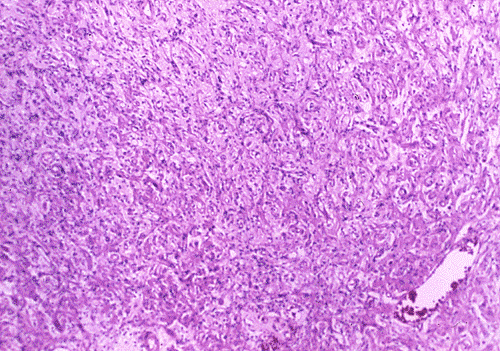

Histopathology: On histologic examination, the cortex lesion (C-L in Panel A) appear fibrous and vascular. It is well demarcated from the white matter (W in Panel A). The cortical lesion respects the grey-white junction and the interface is smooth. These features are better appreciated on Masson's trichrome stain. While one side of the gyrus is replaced by the lesion (C-L in Panel E), normal cortex is present on the other side of the gyrus (C-N in Panel E). White matter (W in Panel E) and the normal cortex (C-N in Panel E) carry a pink hue on Masson's trichrome.he fibrous lesion (C-L in Panel E) does not carry much of this pink hue.  The lesion essentially follow the shape of the gyrus with some cortical thickening (Panel F). On higher magnification, the cortical lesion is highly vascular (Panel B, C, and G). In between the fibrous vascular component, there are entrapped islands of cortical tissue (Panel D, H, and I ). There is a general lack of pleomorphism and mitotic activities in the lesion.

Histologically, the salient feature is a disorganized lesion featured by perivascular meningothelial cells intermingled with a fine, rich vascular network. Although each lesion is unique, increased cortical vascularity and perivascular cellular proliferation are constant findings. Irregularly branched blood vessels extending into the gray matter from the meningeal surface are surrounded by a concentric arrangement of proliferating spindle-formed cells .The overall structure can occur as nodules, whorls, or bands. Islands of cortical tissue with gliosis are often trapped within the lesion. The ratio between meningothelial component and vascular component varies substantially. There are lesions predominantly composed of vascular component or meningothelial component 3. A schwannian component can also occur. There are also cortical meningovascular fibroblastic proliferation and leptomeningeal calcifications that range from faint psammomatous calcification to dense osteoid. Residual neurons entrapped within the lesion may contain neurofibrillary tangles with ultrastructural and immunostaining properties identical to those seen in Alzheimer's disease but there is no deposition of amyloid Ab.